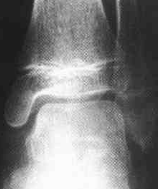

图2-1幼年型特发性关节炎(早期)

左踝关节诸骨质疏松,踝关节前后关节囊肿胀(白箭)

但无明显的关节软骨消失或软骨下骨质破坏表现